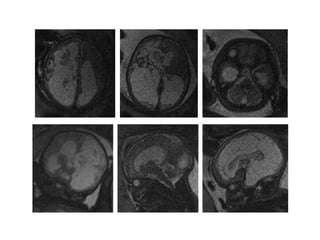

Vitamin K deficient ICH: Cases UH Leuven

Case 1 Case 2 Case 3 Case 4 Case 5 Case 6

Neonatal outcome Died Died Mental retardation Mental retardation Died Died

Eerdekens A, Eur J Pediatr 2010;169(2):191-6

Van Mieghem T, Obstet Gynecol 2008;112:434-6